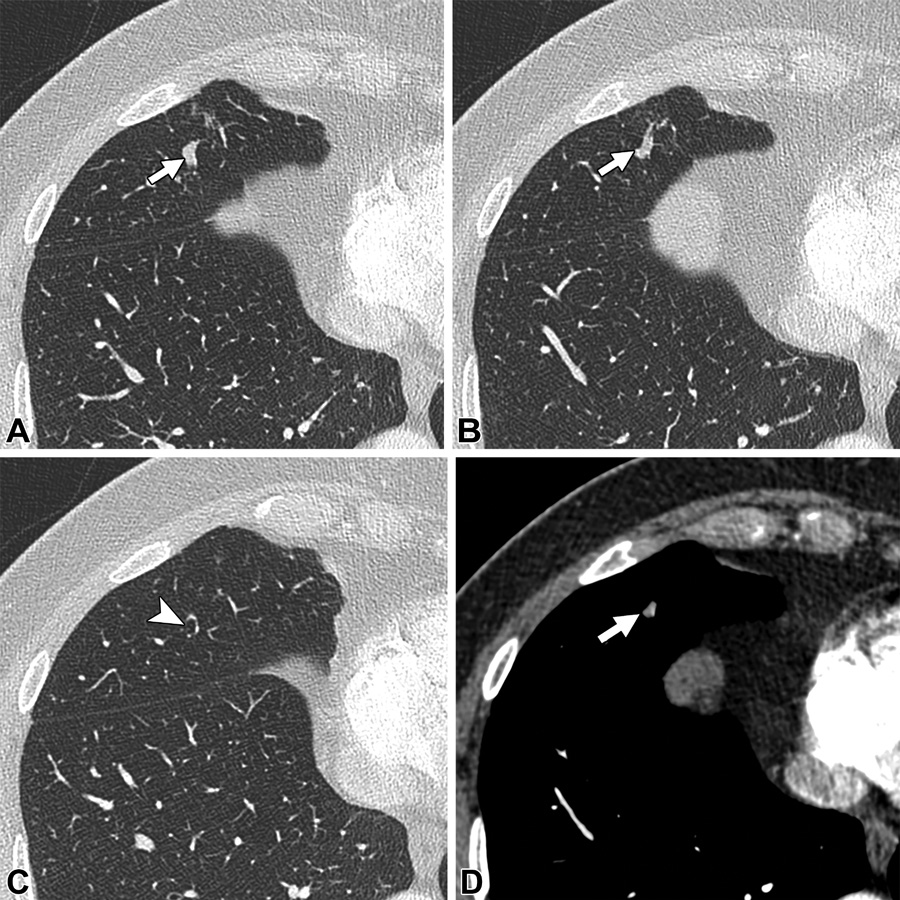

粘液囊肿。68岁男性。(A,B)轴位CT图可见右肺中叶内一个分枝管状结构(白色箭头)。(C)可见近端含气的支气管(白色箭头)。(D)轴位增强CT,病变无强化(白色箭头)。未见引流静脉或供血动脉。以上表现符合粘液囊肿。

肺透光度增加,空气潴留。34岁女性。(A,B)分枝病变(白色箭头)伴周围肺透光度增加及空气潴留(白色圆圈)。(C)病变无强化(白色箭头)。分枝结构提示扩张的支气管,无强化的病变提示粘液栓。

线样肺不张。61岁患者,有遗传性出血性毛细血管扩张症病史。轴位CT增强图,左肺下叶一个没有强化的扩张管状结构(白色箭头),未见病灶,供血动脉及引流静脉。以上表现最符合线样肺不张。